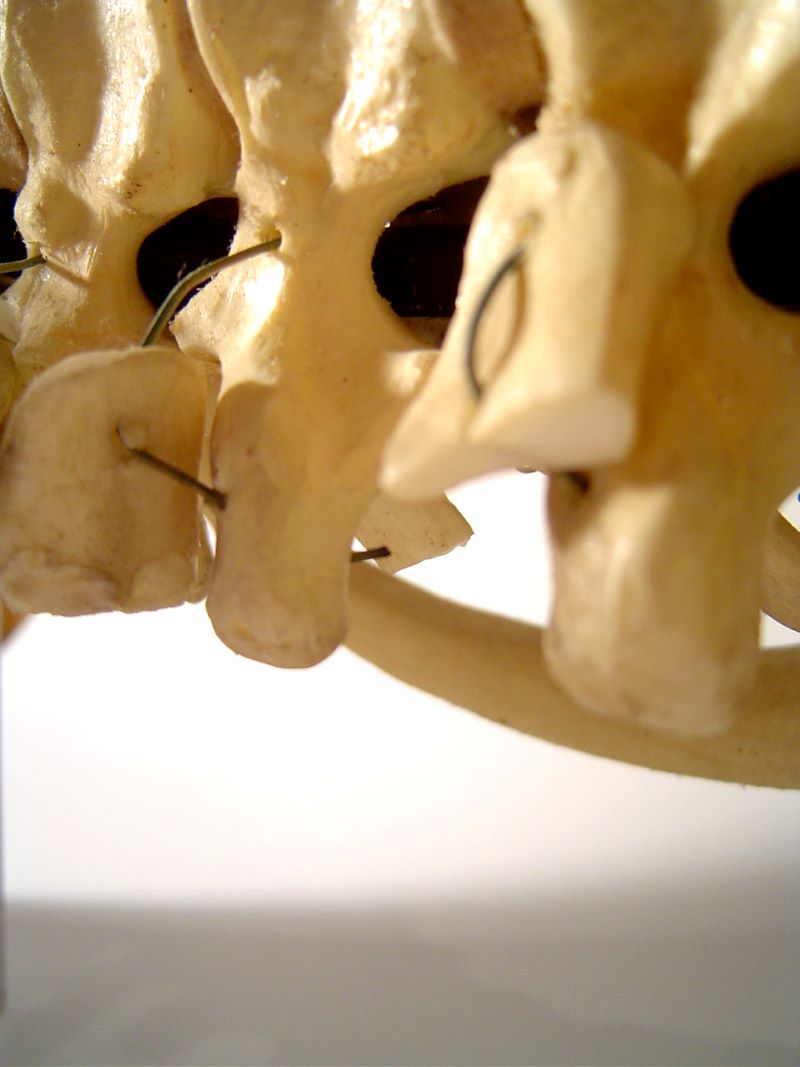

무릎 관절의 퇴행성 변화는 보행 기능에 큰 지장을 초래하며, 통증과 기능 저하가 심각할 경우 인공관절수술이 필요할 수 있다. 이 수술은 많은 환자에게 삶의 질을 회복시켜주는 효과적인 치료법이지만, 고비용 구조로 인해 진입 장벽이 높은 것도 사실이다.